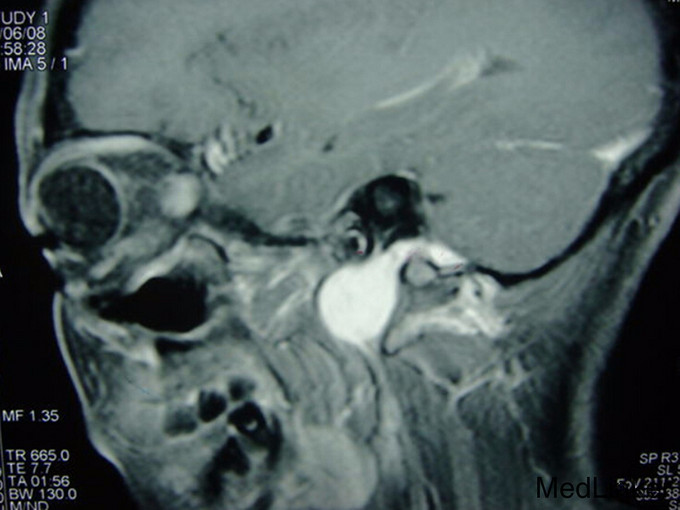

咽部淡红, 无明显充血, 左前腭弓膨隆, 左扁桃体二度肿大, 触诊可于左前腭弓, 扁桃体上极部位扪及一6×5cm大小肿块, 质较韧, 无搏动感, 边界清; 颈部淋 巴结未触及肿大。咽部MRI检查示:左侧咽旁间隙(扁桃体水平)见异常信号肿块, 边缘清楚, 可见完整包膜, 约4.5×3.2cm, 左扁桃体受推移, 鼻咽未见异常改变。

诊断:眼旁间隙肿瘤,性质待查 治疗:完善术前相关检查,全麻下经口腔径路行左咽旁肿物切除术, 术中见左咽旁间隙肿物约6×7cm大小, 包膜完整, 与周围组织分界清, 术中送冰冻病理切片检查示: 考虑“混合瘤”; 术后肿物石蜡病理切片示:左咽旁间隙“涎腺混合瘤”。